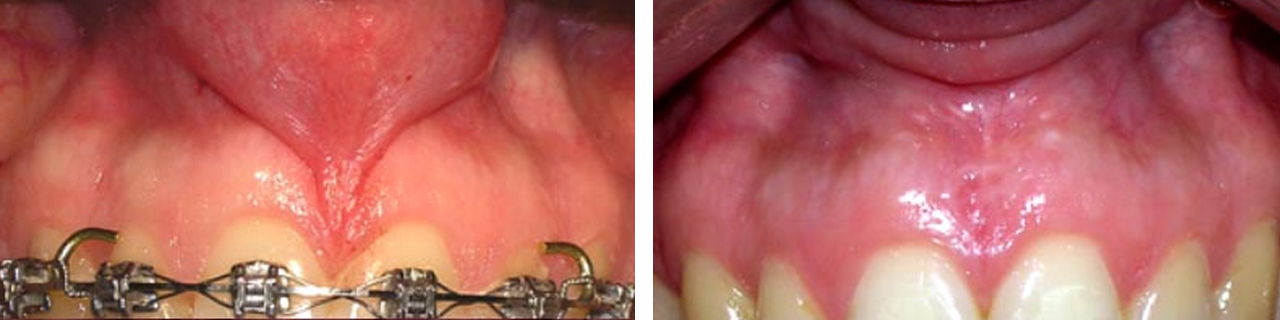

Eliminación de frenillos.